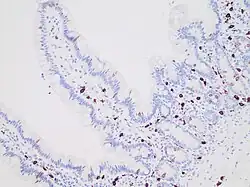

Immunohistochemistry for c-KIT highlights mast cells (darkly stained) in the mucosa of the small intestine.